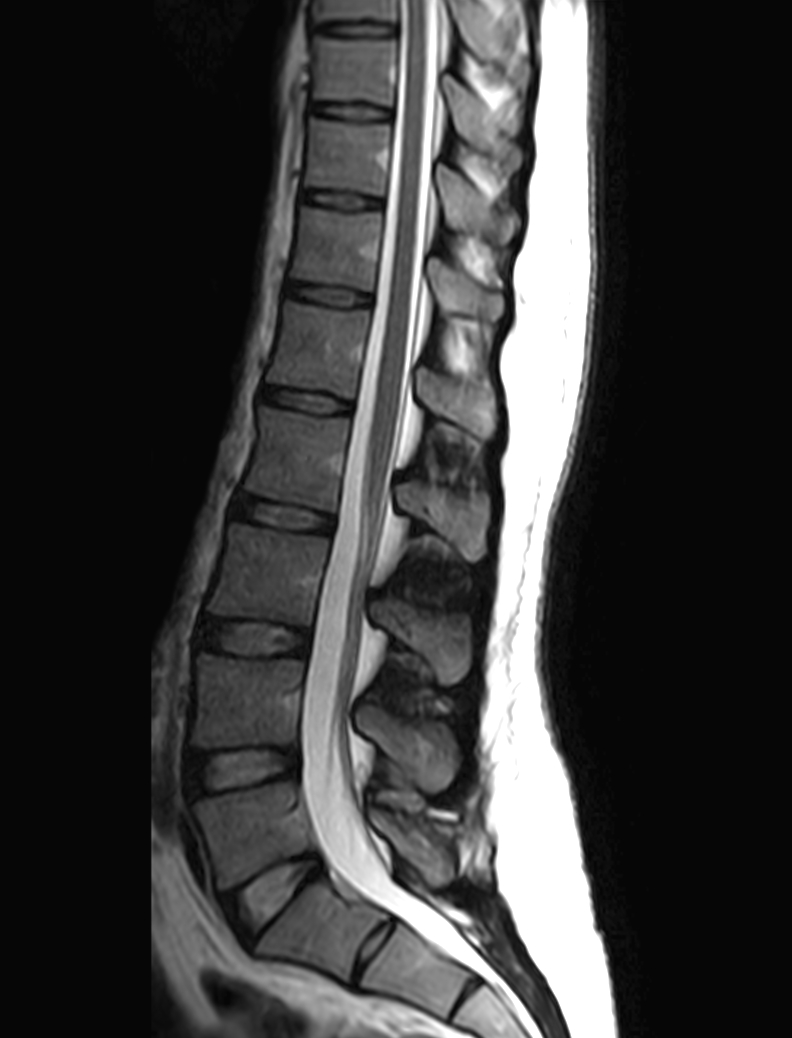

Sagittal mDIXON XD -  T1w TSE (In Phase)